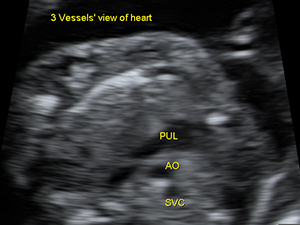

Heart